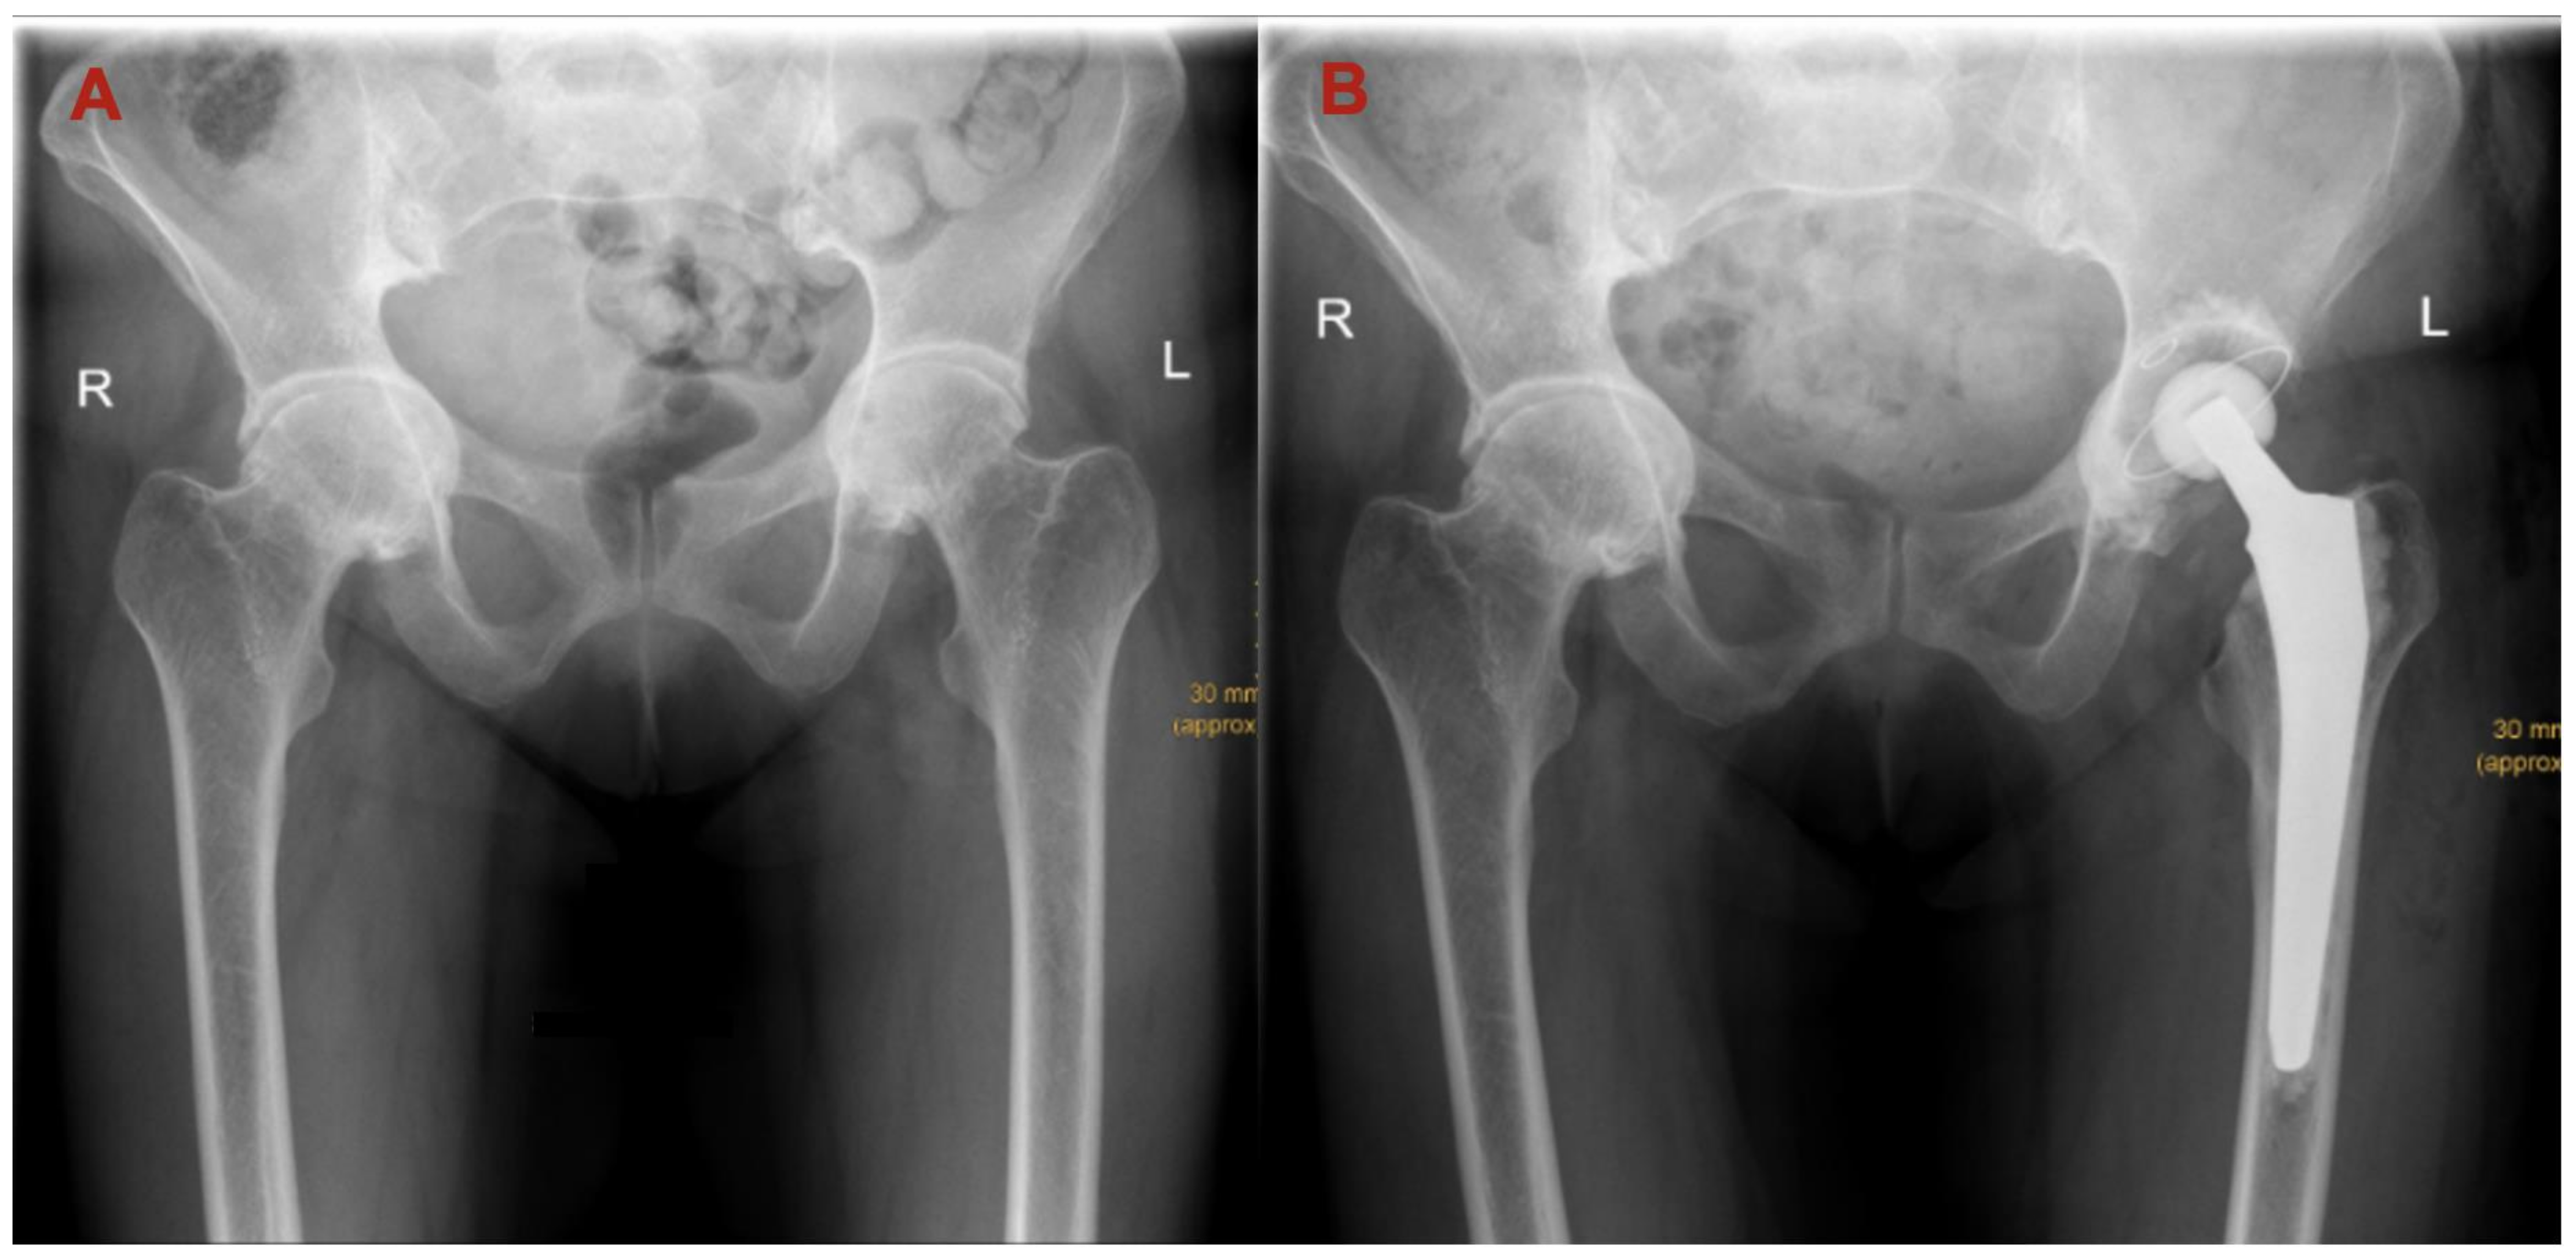

| LCEA (mean ± SD) | 40.41° ± 9.82° | 55.09° ± 9.64° | <0.00 |

| Sharp (mean ± SD) | 36.44° ± 5.15° | 34.04° ± 4.81° | <0.00 |

| Tönnis (mean ± SD) | 6.16° ± 5.70° | 3.12° ± 5.89° | <0.00 |

| Acetabular depth (mean ± SD) | 24.73 mm ± 4.01 mm | 27.92 mm ± 4.67 mm | <0.00 |

| ADWR (mean ± SD) | 334.60 ± 43.33 | 388.50 ± 61.22 | <0.00 |